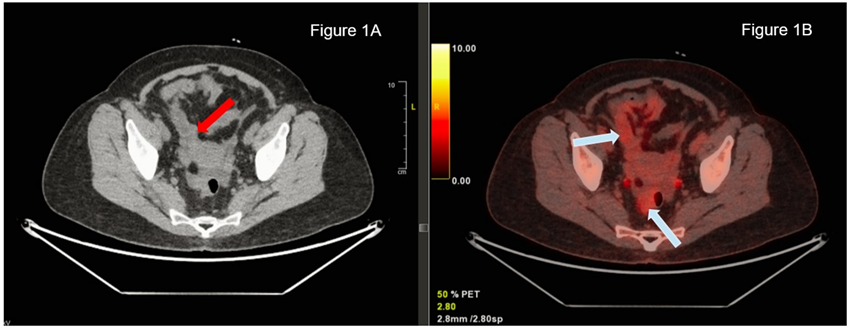

Computed tomography (CT) of the thorax, abdomen, and pelvis revealed splenomegaly, mesenteric panniculitis and small-volume ascites, raising suspicion for a systemic inflammation. Positron Emission Tomography–Computed Tomography (PET-CT) showed metabolically active lymph nodes and mesenteric fat that consists of inflammatory changes, that ruled out a lymphoproliferative syndrome (Figure 1).

Figure 1: Mesenteric panniculitis.

Figure 1A: CT scan: Nonspecific inflammation involving the adipose tissue of the mesenter.

Figure 1B: PET-CT: Nonspecific increased metabolism (FDG uptake) due to inflammation.